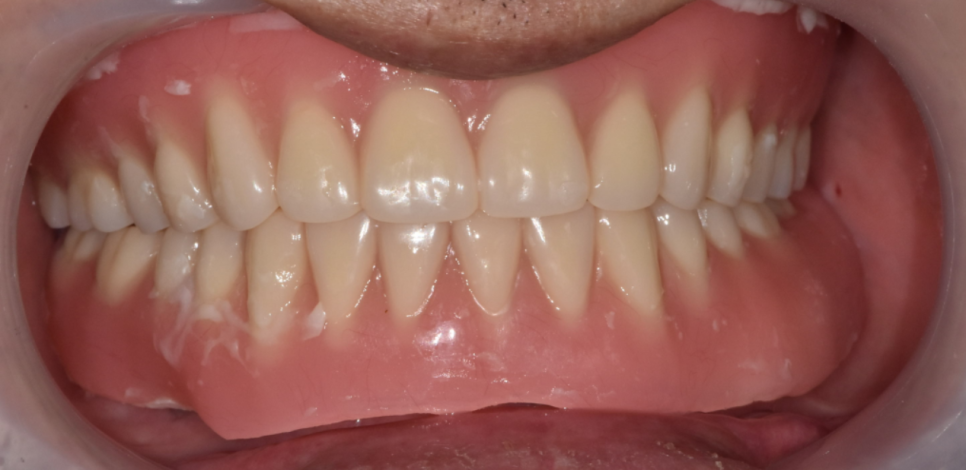

보철물을 바로 제작하기 보다

임시치아로 2주정도 사용할 수 있게 하였습니다.

이게 임시치아인데요.

나쁘지 않죠~?

2주정도 임시치아를 사용해 보시면서 감도 익히시고

보철물의 모양이라던가 색깔 , 높이

환자분과 디테일한 부분들을 상의했습니다.

임시치아 상태에서

씹는게 낯설다고 표현하셨던 환자분이 기억납니다

틀니가 안맞아서

이가 없어서

계속 죽같은 것만 드시다

딱딱딱 치아끼리 부딪히는게 얼마만인지 모르시겠다고요~

임시치아로 씹는 것을 적응좀 하시고

그 뒤에 보철물을 붙여드렸는데요.